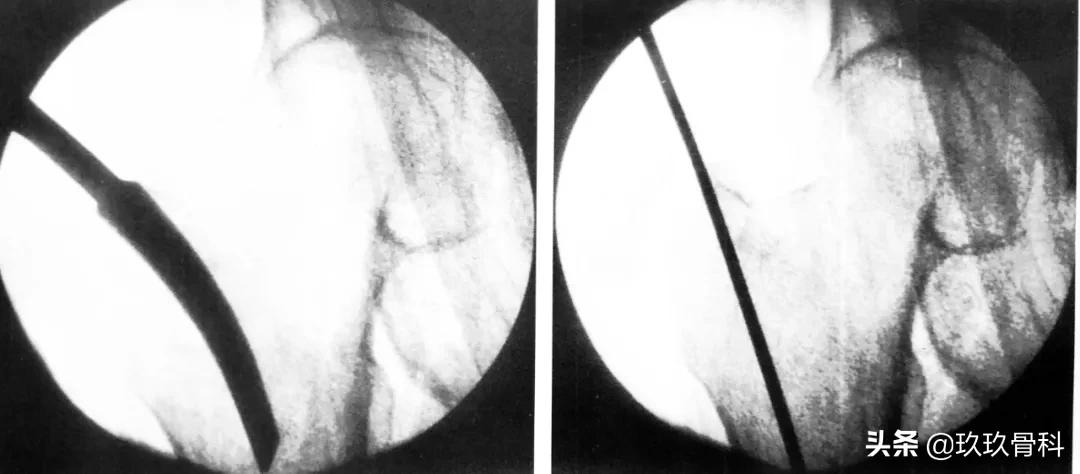

C 形臂下操作步骤,尖端开髓、插入导针

扩髓、主钉置入

正位拉力钉导针位置、侧位拉力钉导针位置